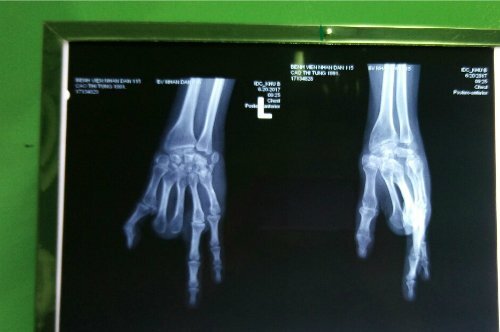

Lấy 2 ngón chân ghép thành ngón tay cho cô gái trẻ

Bệnh nhân bị đứt tay do tai nạn lao động, 7 năm sau được bác sĩ Bệnh viện Nhân Dân 115 lấy hai ngón chân ghép lên bàn tay.